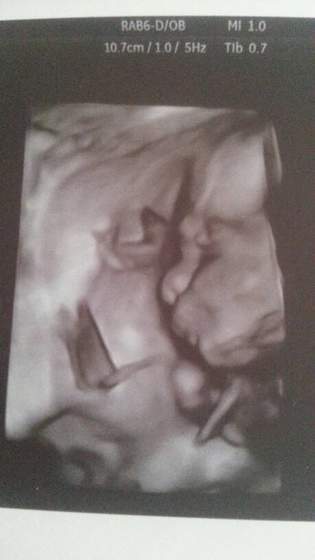

Nasze zdjęcia testów, USG, brzuszków i Maluszków ;)

No to wchodzimy w III trymestr :) Masakra jak to szybko leci :)